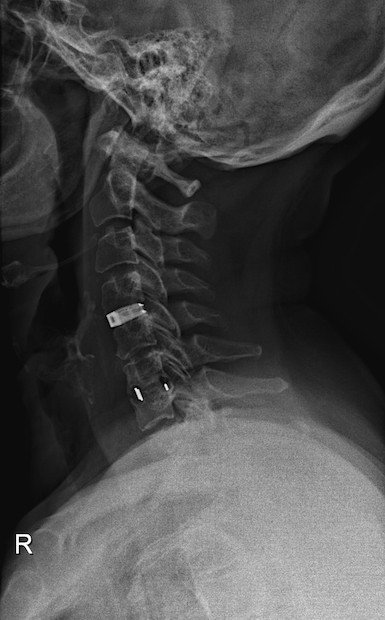

German medical device manufacturer Emerging Implant Technologies (EIT), the first European orthopaedic implant maker to focus solely on manufacturing with 3D printing, recently demonstrated the vast potential of medical additive manufacturing by supplying the first anatomically adapted, 3D-printed titanium fusion implant to a patient with a degenerative cervical spine condition. The technology behind this pioneering effort was 3D Systems’ Direct Metal Printing (DMP) technology, which is capable of building metal objects layer by layer in a variety of metals, in this case biocompatible titanium.

Designed in partnership with 3D Systems and produced using its cloud-based manufacturing services, the porous EIT cervical implant imitates the structure and characteristics of natural trabecular bone, say the developers, allowing the surrounding structures to fuse with it more easily and significantly accelerating the healing process. This sophisticated medical device—with its precise micro-, macro- and nano-structural components—demonstrates the power and potential of infinitely complex 3D printed parts and the incredible accuracy of DMP technology.

Typically, a cervical implant procedure requires bone grafts as well as stock metal implants and comes with a range of undesired outcomes, like implant migration and breakage. As a result, many patients require subsequent operations before the implant can be secured. EIT’s implant, on the other hand, nullifies the need for bone grafts and, with its bone-like structure, provides enhanced bone-implant contact and fusion. At the same time, using patient-specific imaging data and 3D printing, EIT is able to provide implants that fit perfectly with the patient’s anatomy and produce those implants faster and more economically than traditional methods. These custom-fit implants reduce the chance of migrating and actually encourage the bone-implant fusion that is so vital to the success of this procedure. For the patient, this all translates into less time under anaesthesia because no bone grafts are required, a reduced risk of re-operation due to migrated implants and, potentially, a faster recovery.